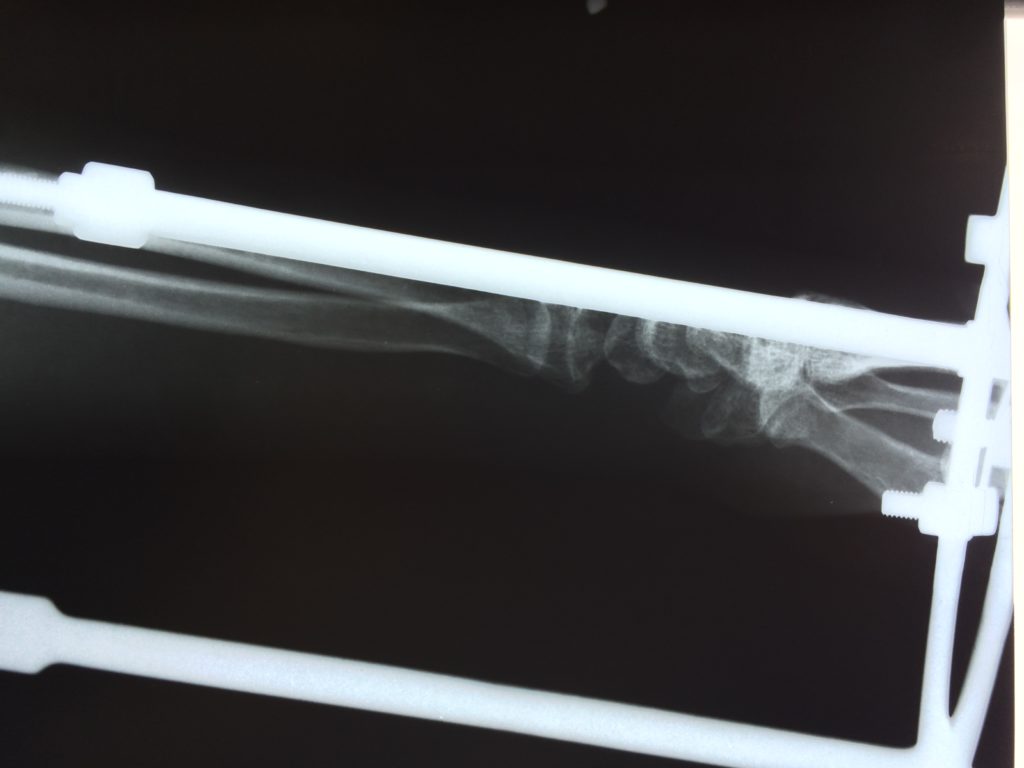

Операция - открытая репозиция, остеосинтез лучевой кости пластиной с костной ксенопластикой материалом "Остеоматрикс". На контрольных снимках в три месяца имеется консолидация перелома, миграции фиксатора нет, имеется остеоинтеграция ксенопластического материала.

Отдаленные результаты через 6 (шесть) месяцев